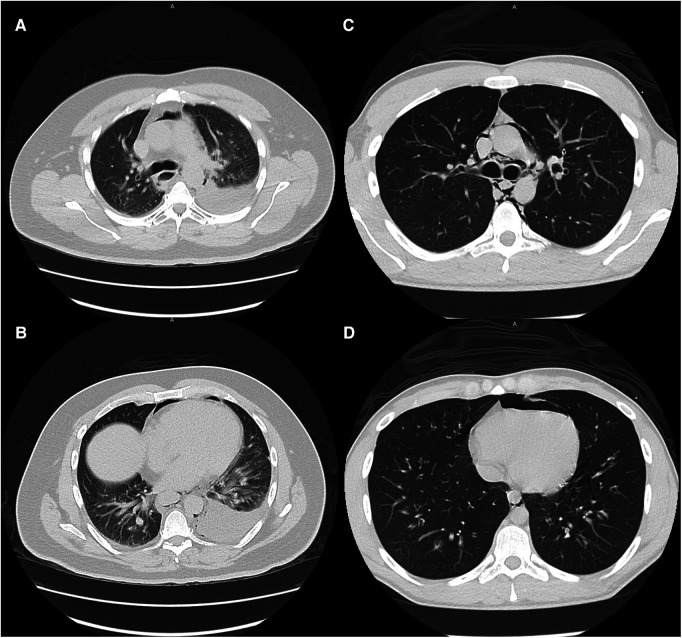

Large and moderate pleural effusions (Figure 2), however, were only found in patients who required operative intervention, and is a radiographic finding that is commonly associated with esophageal perforation (ref. 23). In patients presenting with this finding, suspicion for esophageal perforation should remain high, and dedicated esophageal imaging should not be deferred in the stable patient who does not require emergent operative intervention. Similarly, forceful and/or repeated emesis can lead to full-thickness esophageal disruption, defined as Boerhaave syndrome. As mentioned previously, marijuana use can lead to cannabinoid hyperemesis syndrome, which is relatively rare but occurs most frequently in daily long-term users (ref. 10). Only three of our THC patients reported any form of emesis, of which only one was thought to have cannabinoid hyperemesis syndrome. This patient was worked up with a CTE that showed no leak and he was managed conservatively. As illustrated with this patient, any history of forceful or repeated bouts of emesis should prompt the provider to be concerned about Boerhaave syndrome, and the patient should be worked up appropriately, regardless of marijuana use status.